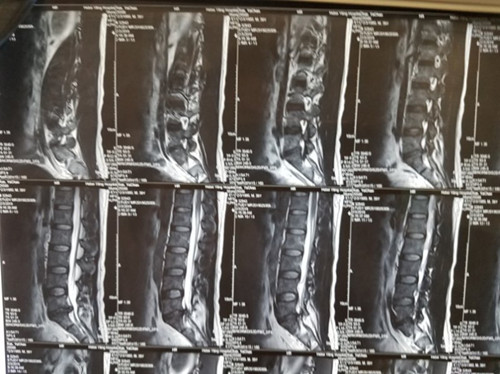

腰5骶1椎間盤突出